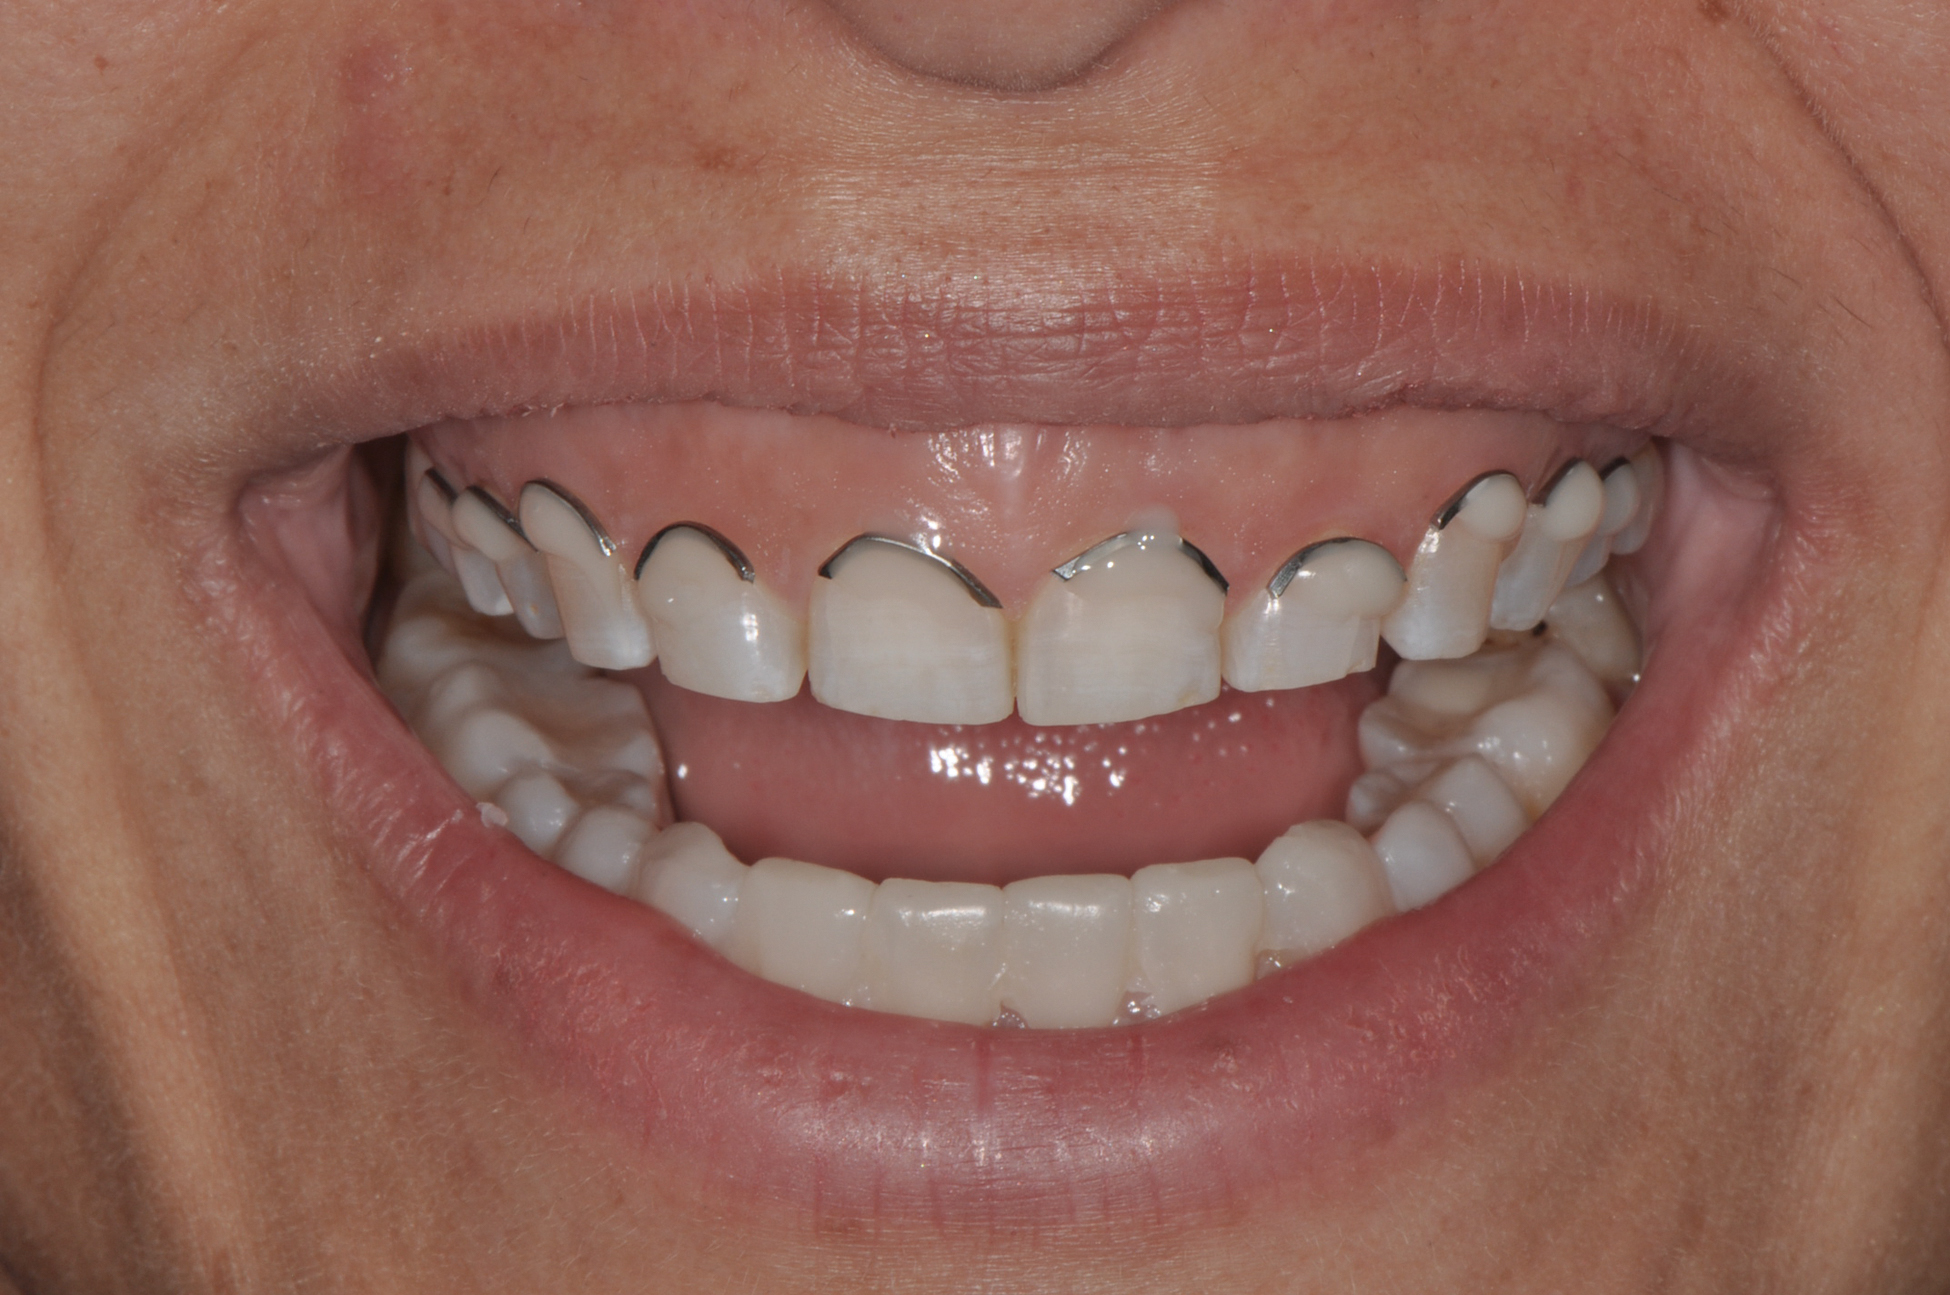

Fig 1. Patient with a gummy smile.

Figure 1

Fig 2. Resolution of gummy smile after treatment in patient shown in Fig 1.

Figure 2